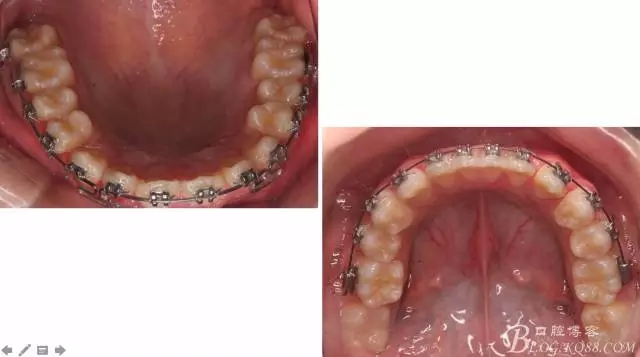

一晃快兩年了,我覺得關(guān)節(jié)重建及咬合穩(wěn)定,再加上患者的急迫愿望,我們拆除了矯正器。

尖牙關(guān)系中性,磨牙關(guān)系中性,咬合鎖結(jié)良好!